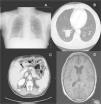

Two weeks after histologic confirmation of the metastases, the patient presented to the emergency department with productive cough with whitish sputum and lower chest pain on both sides. The symptoms had appeared 3 days earlier. A chest radiograph showed a poorly defined radiopaque area in the basal region of the right lung field (Fig. 3A). In view of the patient's medical history, a computed tomography scan was performed, confirming the presence of a large mass measuring 4.3cm in the right lower lobe, and showing multiple pulmonary nodules and mediastinal lymph node involvement (Fig. 3B). Metastases were also observed in the liver, around the kidneys, and in a suprarenal gland (Fig. 3C), as well as in subcutaneous tissue and muscle tissue. One month later, the patient once again presented to the emergency department with disorientation and generalized tonic-clonic seizures. Brain magnetic resonance imaging revealed a prominent left choroid plexus and an irregularly shaped, high-uptake image consistent with a metastatic lesion (Fig. 3D). Following gradual deterioration in general health, the patient died just 6 weeks after the diagnosis of cutaneous metastases.

A, Anteroposterior chest radiograph showing a poorly defined radiopaque area in the basal region of the right lung field. B, Thoracic computed tomography scan showing a large mass measuring 4.3cm in the right lower lobe and multiple smaller pulmonary nodules. C, Abdominal computed tomography scan showing intrahepatic, perirenal, and right suprarenal metastases. D, Brain magnetic resonance imaging showing a prominent left choroid plexus and an irregularly shaped, high-uptake image consistent with a metastatic lesion.